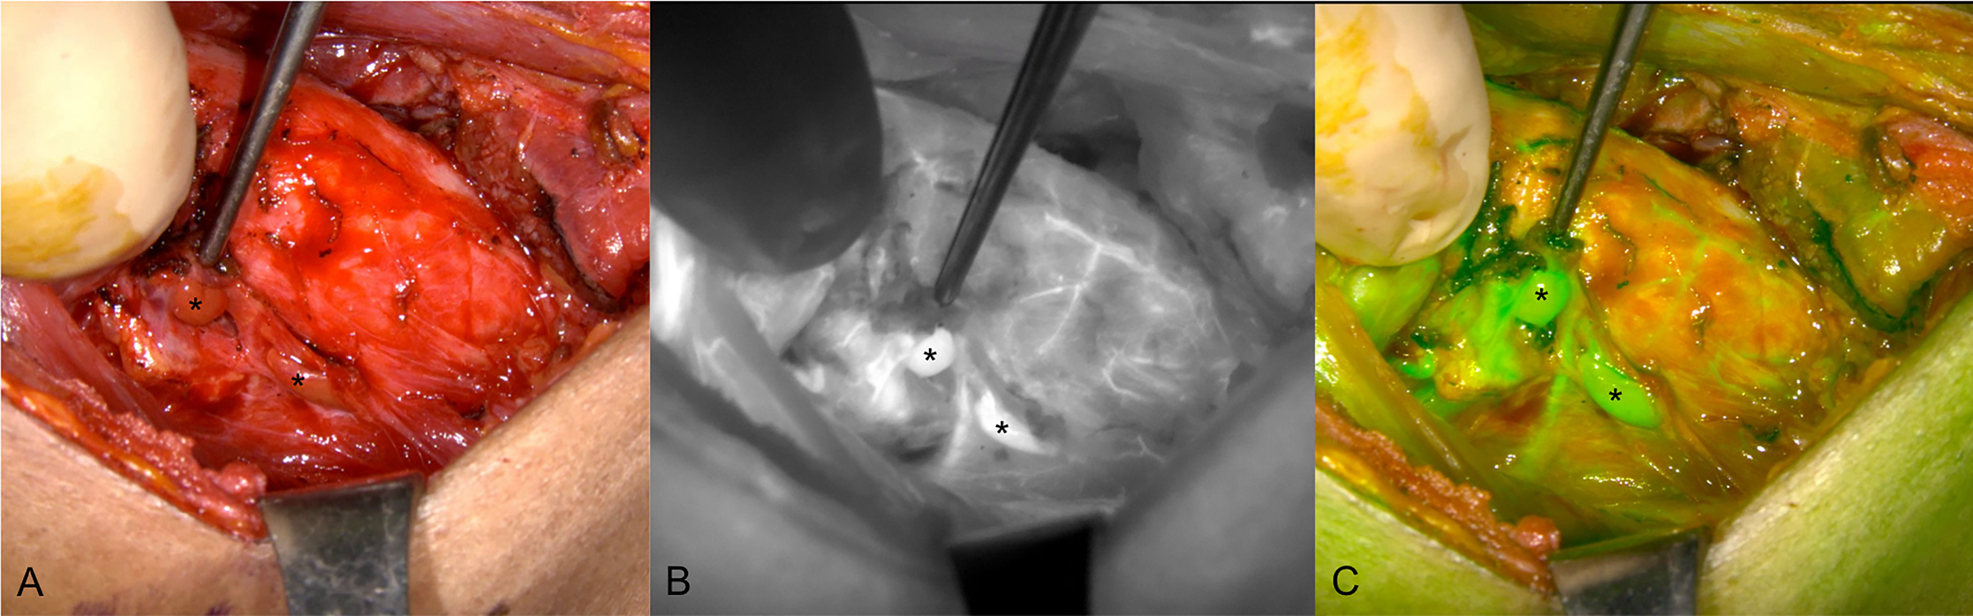

Most recently, ICG has been proposed to be the most suitable agent for the intraoperative assessment of the PG vascularization, which is closely correlated with parathyroid function (Figures 7 and 8) [56, 60], [61], [62], [63], [64]. Many studies have evaluated the use of ICG angiography to identify normal PGs and assess their perfusion in thyroidectomies (Table 3). These studies suggest that ICG angiography is a safe, feasible, effective, and easy technique to identify and preserve PGs [65]. Owing to the contribution of ICG angiography to intraoperative decision-making, the technique may be widely used in the future, especially as new applications are developed. For example, the technique is being developed for mini-invasive and robotic surgery applications, including the transoral endoscopic thyroidectomy vestibular approach and the robotic bilateral axillo‐breast approach [66], although studies are limited.

Indocyanine green (ICG) angiography images of the right side parathyroid glands (PGs) (indicated with *) after thyroidectomy surgery. (A) Unaided visualization of the tissue. (B) Near-infrared autofluorescence (NIRAF) grayscale image and (C) Green fused image showing two well-vascularized PGs after injection of ICG.